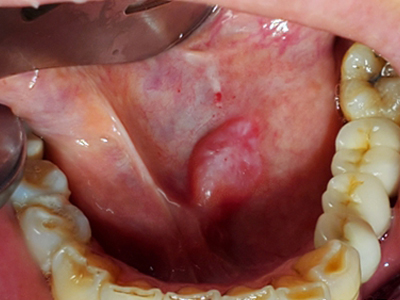

舌下腺囊肿舌头下面右侧有一个紫色包块图

舌下腺囊肿出现在口底舌系带一侧,表现为紫蓝色的隆起性包块,形态大致呈球形,界限清楚,质地柔软,囊肿增大后因破裂流出黏液。